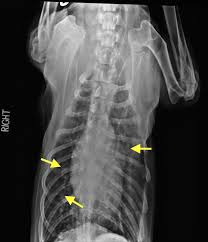

Symptoms Of Metastatic Lung Cancer In Dogs : Signs Chemo Is Not Working How To Make The Decision - However, some dogs only experience weight loss (despite a good appetite) and/or lack of energy.. Other symptoms include exercise intolerance, lethargy and weight loss. In general, symptoms develop based on where the metastatic cancer is located, how invasive it is and how long it has been present. Symptoms of lung metastases pulmonary metastases may not produce symptoms. Symptoms of lung cancer in dogs usually there are no symptoms in the early stages of canine lung cancer. In the beginning stages, many dogs show no clinical signs.

Specific signs will depend on where the tumor is located and may include a swollen paw, eye discharge or sores in the mouth. Most common symptoms anemia / coughing / lethargy / loud breathing / redness / swelling. This just means that the route of testing is usually different for each dog. Computed tomography (ct scan) can be performed to identify some of these lung tumors. When metastatic cancer spreads to the bones, the primary symptoms may be hesitancy to walk around or climb stairs, or anything that would cause pain to.

In the beginning stages, many dogs show no clinical signs. Pulmonary adenocarcinoma is cancer of the lungs, which can be primary (originates in the lungs) or secondary (originates somewhere else in the body), is a serious disease that can be fatal if not found and treated early. Metastic neoplasia (cancer) in dogs. That said, here are some general signs and symptoms that indicate the possibility of lung cancer: Almost 70% of dogs with lung cancer experience metastasis to other parts of the lung, meaning treatment may only prolong their life rather than eliminating the disease completely. However, some dogs only experience weight loss (despite a good appetite) and/or lack of energy. Metastatic lung tumors are tumors originating from a cancer elsewhere in the body which has spread to the pet's lungs. Symptoms of lung cancer in dogs usually there are no symptoms in the early stages of canine lung cancer. As the cancer grows, dogs may develop a cough, difficulty breathing, and other symptoms. Lung tumors are relatively rare in dogs, accounting for only 1% of all cancers diagnosed. Life expectancy of a dog with lung cancer. The protocol will often differ based on the symptoms your dog presents with. Computed tomography (ct scan) can be performed to identify some of these lung tumors.

In general, symptoms develop based on where the metastatic cancer is located, how invasive it is and how long it has been present. In the absence of diagnostic testing, it can be challenging to detect lung cancer in dogs. Cancer of the lungs is a progressive disease, meaning it gets worse over time. That said, here are some general signs and symptoms that indicate the possibility of lung cancer: The dog may cough up blood, but not mucus. At this stage, the tumor can be removed through surgery. The symptoms of metastatic cancer in dogs are not universal. Chronic coughing seems to be the most common abnormality that is seen in dogs with lung cancer. Adenocarcinoma of the lung in dogs. Unlike some other types of cancer, there are some concerning symptoms that arise in the earlier stages of primary lung cancer for dogs that should immediately alert you that something is wrong. Lung cancer in dogs symptoms the symptoms of lung cancer are coughing (which may produce phlegm or blood), exercise intolerance (lethargy), loss of weight or loss of appetite and other respiratory symptoms such as difficulty breathing or shortness of breath. On top of dogs presenting symptoms derived from the primary tumor, in advanced cases, dogs will also show signs of lung cancer. Symptoms of lung metastases pulmonary metastases may not produce symptoms.